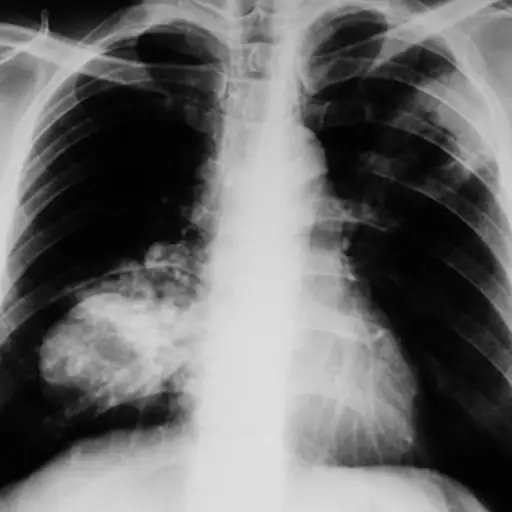

小细胞肺癌

小细胞肺癌(SCLC)通常称为燕麦细胞癌,据据此占10-15%的肺癌AEMERICAN癌症学会。这些癌症迅速蔓延,但对化疗比NSCLC更快,lungcancer.org.报告。

最具侵略性的肺癌形式:小细胞肺癌

SCLC是最具侵略性的肺癌形式。它通常从胸部中心开始呼吸管,并迅速蔓延到身体的其他部位,包括大脑,肝脏和骨骼。